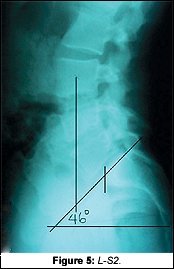

The new x-rays showed significant changes to the neck and low back. The most obvious and most important was the change on the lateral L-S. Tony's sacral base angle went from 56Á to 46Á (Fig. 5). Knowing that normal is 36Á-42Á, this improvement was tremendous. Tony demonstrated many improved findings on his functional re-examination as well.